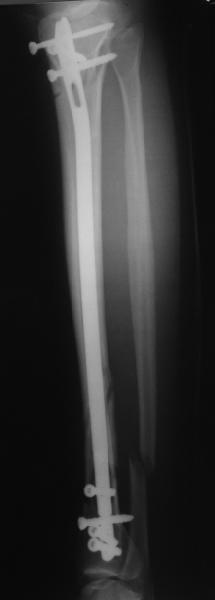

Alexander Chelnokov 22 Май 2006, 00:35

Сделали все-таки стержнем. На всякий случай просверлил дополнительное проксимальное отверстие, так что получилось три 45-градусных винта.

В дистракторе провеи спиц поболше в прокисмальном отделе, чтобы не разобщить фрагменты при сгибании колена. Комментарии и критика приветствуются.

We proceeded with nailing using a small wire distractor, with few wires at the proximal end to prevent displacement with forced knee flexion. Images attached. Comments and critics are welcome.

It is often a problem nailing upper tibial fractures. There is a tendency to apex anterior angulation as well as valgus alignment. Your entry point on the AP view seems to have been kept the same. How did you manage to maintain alignment? Any intra-operative pictures of your technique?

The lateral view shows your entry point to be quite posterior and I think this is recommended to avoid anterior angulation. Were you concerned about intra-articular penetration?

Overall an excellent post-op x-ray. Well done.